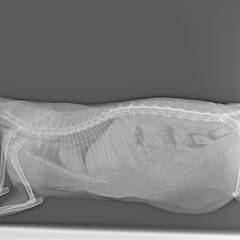

Ярко выраженная болезненность в области крестца, на обезболе полегче. По результатам приема невролога проведена миелография - множественная компрессия, возможно опухоль, возможно грыжа, нужно удалять...